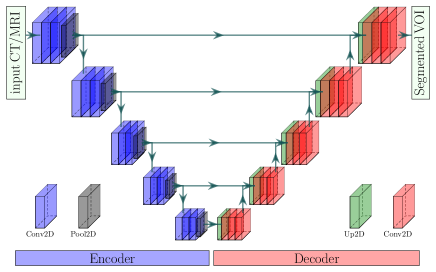

Segmentation of medical image has attained enormous progress notably since after the proposing of UNet [31]. Currently, CNN-based networks have been extensively practiced for the medical imaging domain, exceeding conventional image analysis techniques relying on hand-crafted features [53]. However, the CNN-based network for segmentation incorporates two fundamental elements: the encoder and the decoder [31]. An encoder consists of convolutional and pooling layers. The convolutional layers produce feature maps, whereas the pooling layers continuously decrease these feature maps’ dimension to gain more critical features with more eminent spatial invariance [17]. The decreased resolution feature maps also enlarge the maps’ field-of-view and diminish the computational expense [54]. The decoder projects the distinctive lower resolution features discovered by the encoder onto the higher resolution pixel space to achieve a compact pixel-wise labeling [55]. However, the simple encoder-decoder network, named EDNet, in our implementation is depicted in Fig 4.

The encoder in EDNet is a VGG-16 [56] with the pre-trained weight on ImageNet [57], which has five Convolutional Blocks (CB) and thirteen convolutional layers. Each CB’s output is an input to the next CB through a pooling layer with a stride of . Hence, the encoder’s output feature map has a resolution of for an input resolution of . However, the decoder has five blocks to obtain the input resolutions of the output WHS masks (), where we apply 2D upsampling, with a stride of , convolution with a kernel of , and a batch normalization [58] in each decoder block.

However, the decreased feature maps due to pooling undergo spatial knowledge elimination injecting roughness, poor border knowledge, checkerboard artifacts, over-, and under-segmentation in the segmented substructures [17, 54, 31, 59]. To overcome these problems, the authors in [31] introduced skip connections in a UNet, permitting the decoder to retrieve the associated features discovered at all encoder steps that were missed due to subsampling in the encoder. The feature maps from the encoder’s antecedent layers are concatenated with the decoder’s identical scale through the appliance of skip connections. Applying the skip connection of the popular UNet, we propose a VGG-UNet, where we have also employed the VGG-16 network as an encoder, as shown in Fig. 5.

In our VGG-UNet, we apply the skip connections holding ladder-like compositions [60] motivated by UNet to succeed in the pooling weaknesses. All pooled layers of our network are concatenated channel-wise to a deconvoluted feature map with identical dimensions, where it acts as an offsetting link for the spatial knowledge dropped due to subsampling in the encoder.